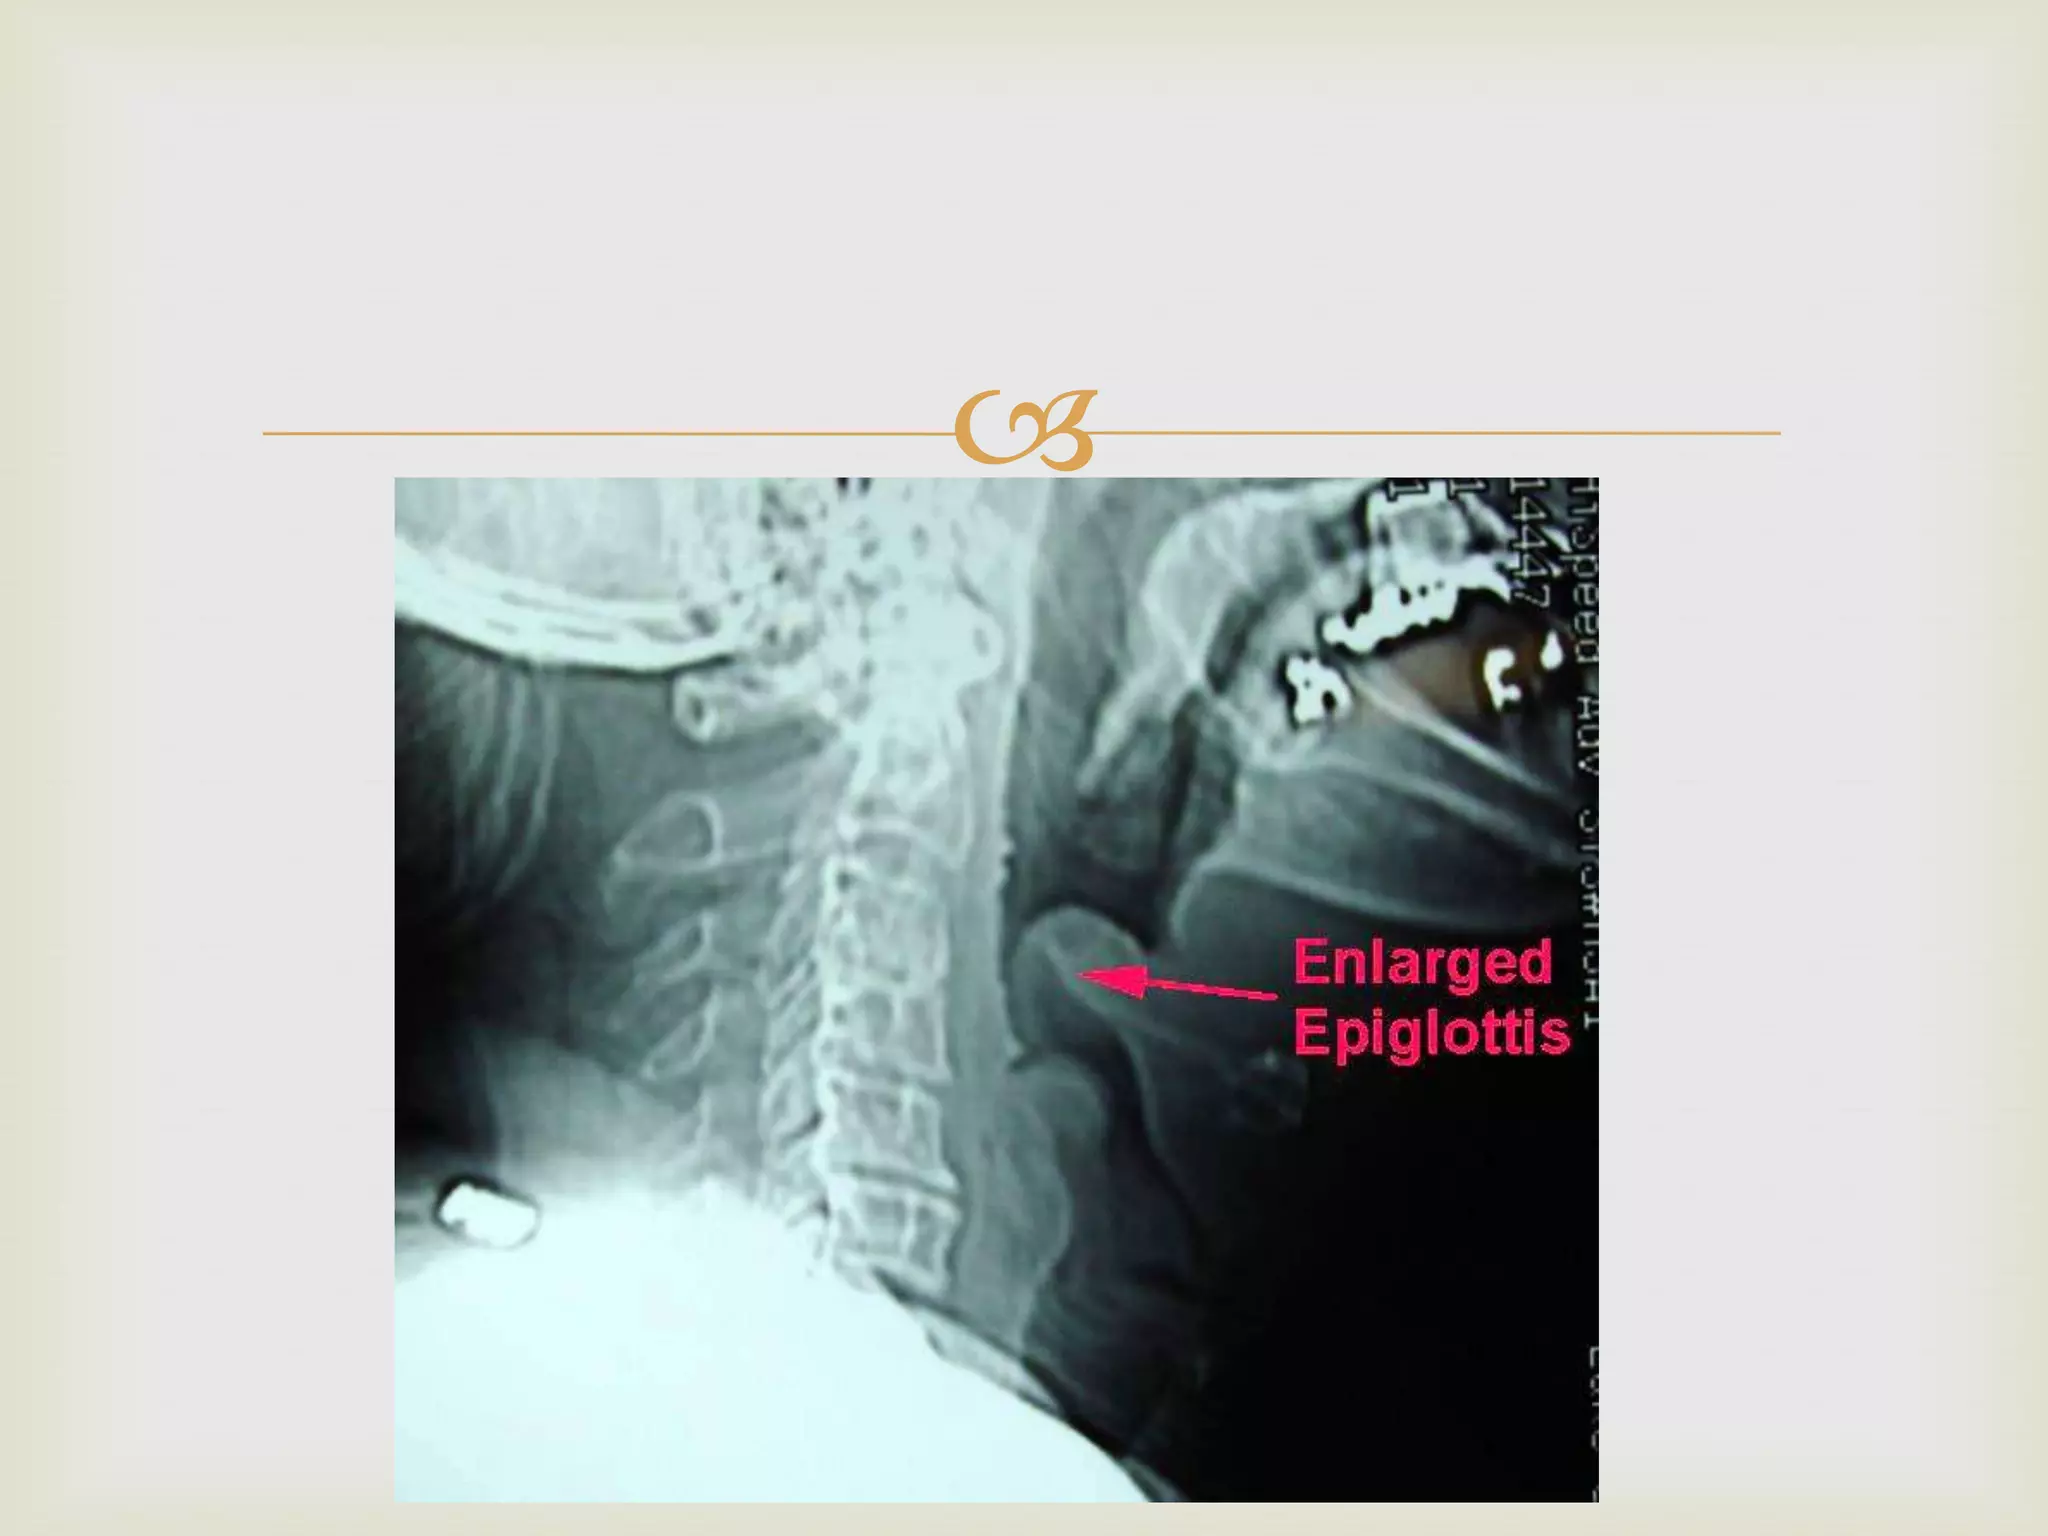

 DIAGNOSIS:

 “CHERRY RED”APPEARANCE OF EPIGLOTTIS ON

LARYNGOSCOPY

 THUMB SIGN ON LATERAL NECK RADIOGRAPH

ACUTE EPIGLOTTITIS